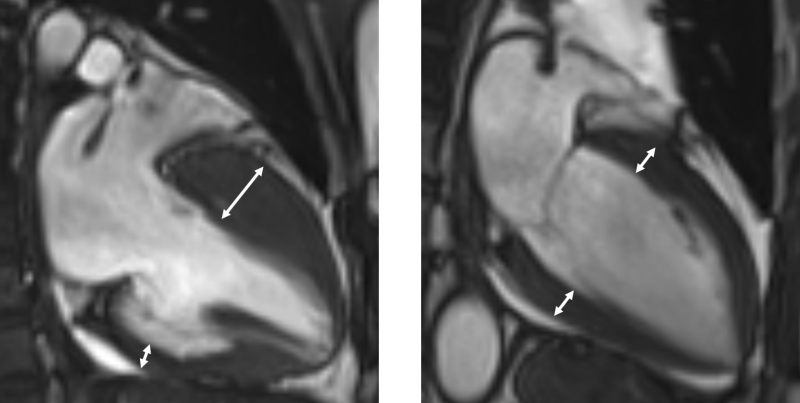

진단은 심장초음파, 자기공명영상 등 영상검사를 통해 이뤄지며, 비후된 심근 내에 섬유화가 진행돼 있거나, 근육조직이 지방조직으로 변성이 돼 있는 상태가 관찰된다. 하지만 이 같은 조직변성이 없는 비후성 심근병증도 있는 만큼 전문의의 종합적 판단이 중요하다.